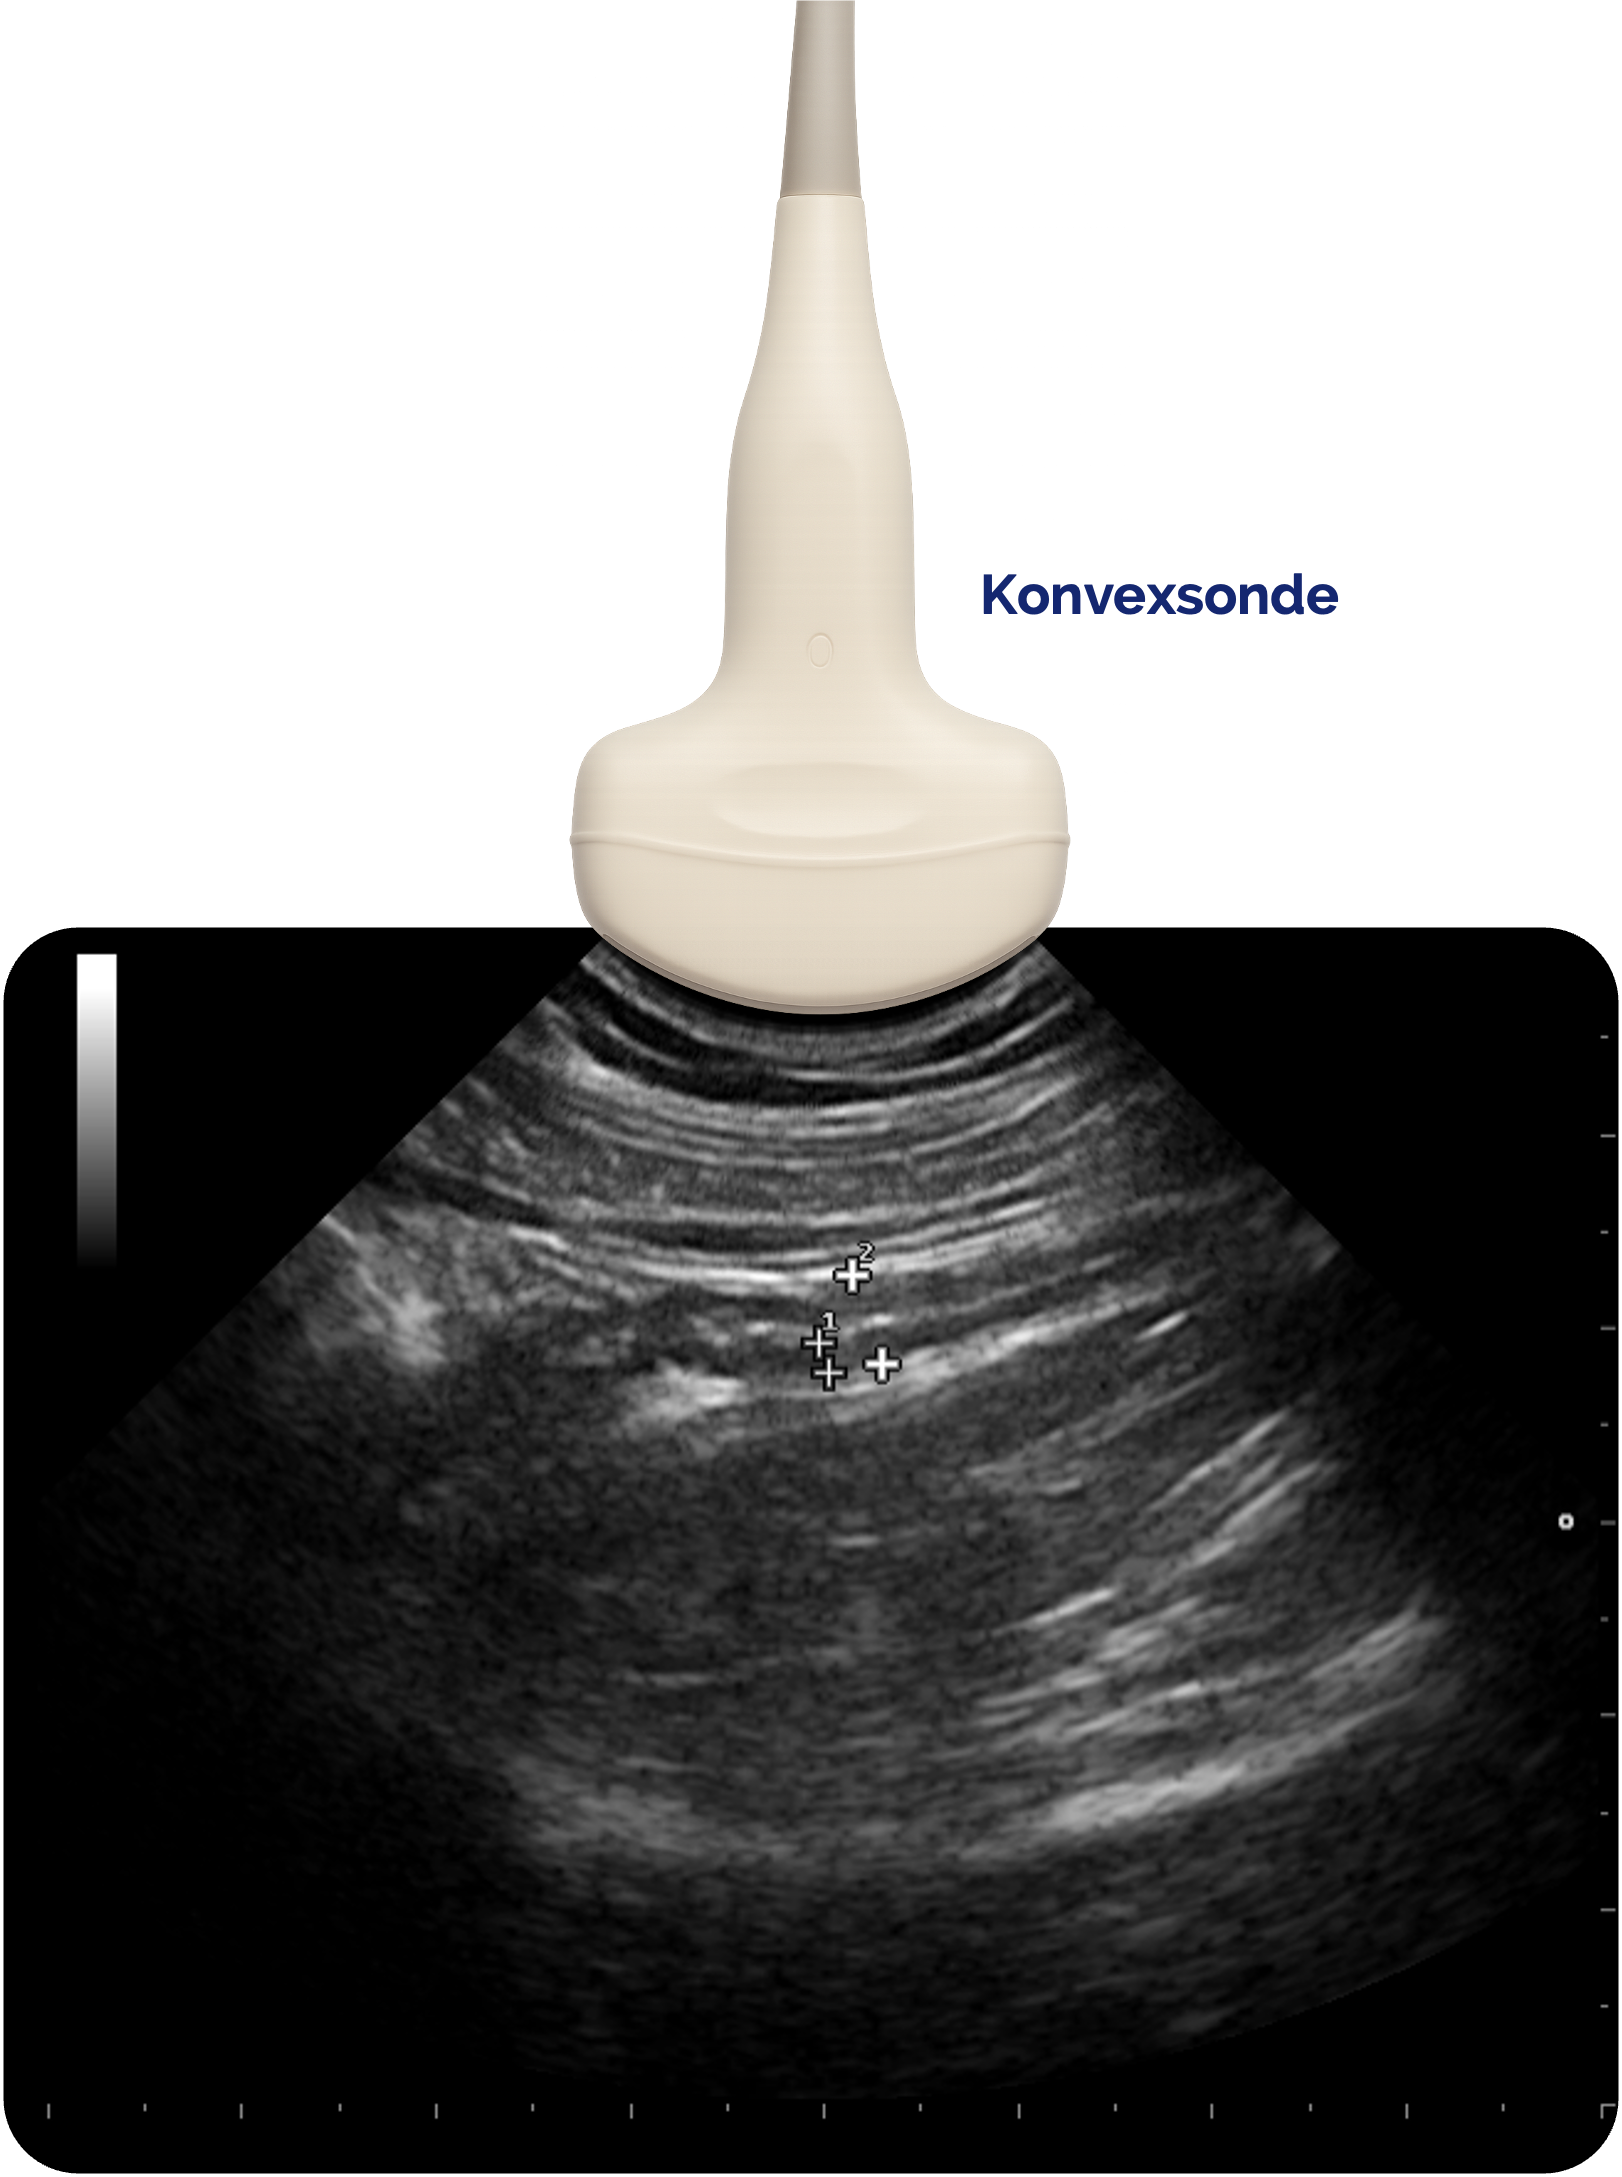

Die Konvexsonde hat einen gebogenen Schallkopf und arbeitet mit mittleren Frequenzen (3–5 MHz). Dadurch erreicht sie eine gute Balance zwischen Auflösung und Eindringtiefe. Das Schallfeld ist fächerförmig, wodurch sich große Tiefenbereiche darstellen lassen.

Konvexsonde Darstellung des Appendix vermiformis. Hohe Eindringtiefe, weniger Details, fächerförmiges Bild